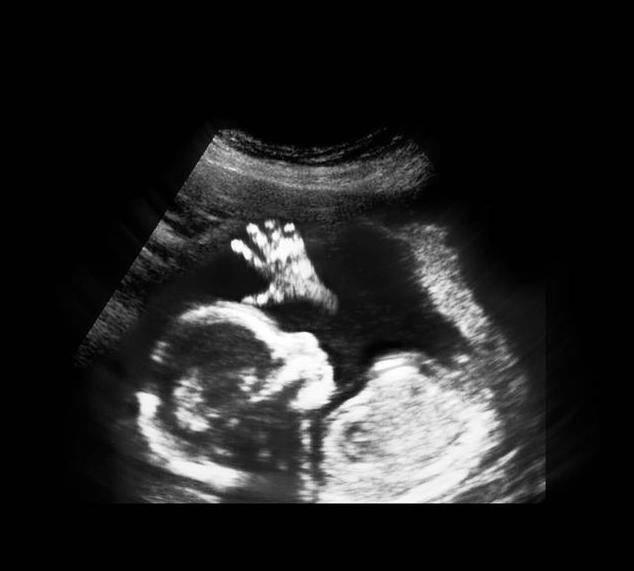

进入了16周,胎儿具备了很多本领,比如吞咽羊水、排出尿液、玩耍脐带、开始有了妈妈能够感受到的胎动,胎儿生殖器官的发育开始可见。